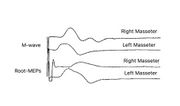

| 13:54, 5 February 2023 | Bruxer MEP.jpeg (file) |  |

440 KB | 1 | |

| 13:54, 5 February 2023 | Bruxer Jaw jerk.jpeg (file) |  |

756 KB | 1 | |

| 17:31, 26 February 2023 | Bruxer SP1.jpeg (file) |  |

141 KB | 1 | |

| 17:31, 26 February 2023 | Recovery cycle.jpeg (file) |  |

54 KB | 1 | |

| 13:53, 5 February 2023 | Bruxer SP2.jpg (file) |  |

780 KB | 1 | |